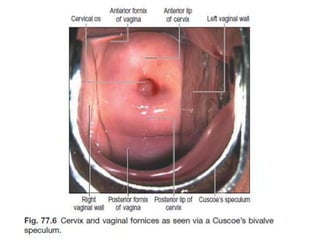

ENDOSCOPY

ESOPHAGUS